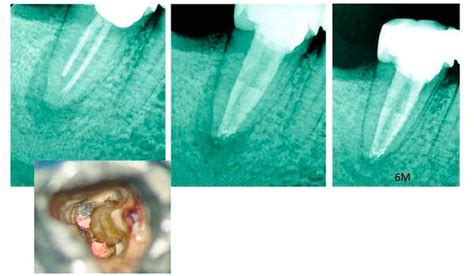

Vor der eigentlichen Aufbereitung der Wurzelkanäle muss deren Länge festgestellt werden. Nur so ist es möglich, den Kanal genau bis zur Wurzelspitze (Apex) aufzubereiten. Eine genaue Messung (Endometrie) erfolgt dann mit dem elektronischen Längenmessgerät, das beim Einführen des Wurzelkanalinstruments die exakte Entfernung zur Wurzelspitze (Apex) angibt. In Zweifelsfällen kann zusätzlich eine Röntgen-Messaufnahme mit Darstellung der zuvor eingeführten Kanalfeilen sinnvoll sein.

Füllung der Wurzelkanäle

Die gereinigten, desinfizierten und getrockneten Wurzelkanäle werden nun bis zur Wurzelspitze möglichst dicht mit einer Wurzelfüllung verschlossen. Dazu wird ein dickflüssiger Zement (Sealer) und Stifte aus Guttapercha in den Kanal eingeführt. Die Guttapercha kann auch mit speziellen Instrumenten (Plugger) komprimiert werden (Kondensation) oder durch Hitze erweicht werden (thermoplastische Wurzelfüllung) um auch die Verästelungen der Wurzelkanäle (sogenannte Seitenkanäle) bestmöglich abzudichten.

Verschluss des Zahnes und Röntgenbild

Nach der Wurzelfüllung wird der Zahn von oben mit einer Kunststoff-Füllung (Komposit) bakteriendicht verschlossen. Der hermetische Verschluss ist sehr wichtig, da der Wurzelkanal ansonsten wieder durch Bakterien aus der Mundhöhle besiedelt wird. Eine Röntgen-Kontrollaufnahme dokumentiert am Ende die durchgeführte Wurzelfüllung.